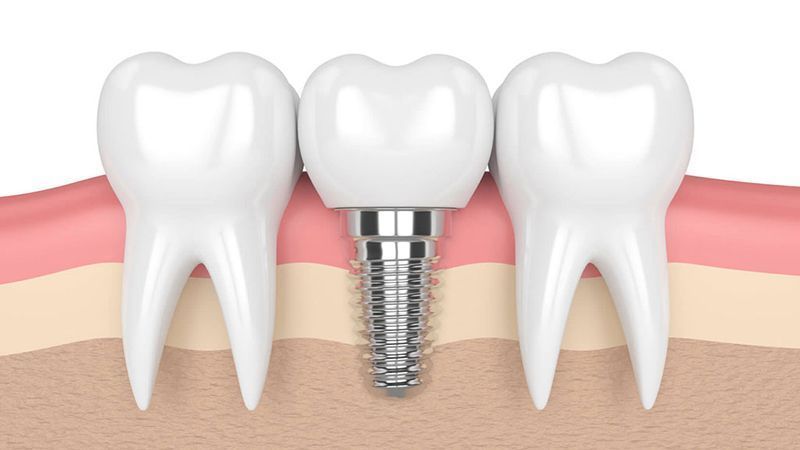

TRỒNG RĂNG IMPLANT Ở ĐÂU TỐT ĐÀ NẴNG? CHI PHÍ BAO NHIÊU?

Trồng răng Implant ở đâu tốt Đà Nẵng là câu hỏi được nhiều khách hàng quan tâm. Đây là kỹ thuật nha khoa phức tạp, do đó cần tìm đến nha khoa có Bác sĩ giỏi và thiết bị hiện đại. Cùng Nha Khoa Đại Nam tìm hiểu trong bài viết dưới đây!

TRỒNG RĂNG IMPLANT Ở ĐÂU TỐT BÌNH ĐỊNH?

Trồng răng Implant giúp khôi phục khả năng ăn nhai trọn đời ở người mất răng. Đây là kỹ thuật có xâm lấn nên việc lựa chọn nha khoa uy tín là rất quan trọng. Bài viết dưới đây chia sẻ với khách hàng trồng răng Implant ở đâu tốt Bình Định, cùng với đó là các kiến thức y khoa về phương pháp này.

TRỒNG RĂNG IMPLANT Ở ĐÂU TỐT NINH THUẬN?

Trồng răng Implant là phương pháp giúp khôi phục tính thẩm mỹ và chức năng ăn nhai của răng. Vậy trồng răng Implant ở đâu tốt Ninh Thuận, các tiêu chí lựa chọn nha khoa trồng Implant? Hãy cùng Nha Khoa Đại Nam tìm hiểu trong bài viết dưới đây.

TRỒNG RĂNG IMPLANT Ở ĐÂU TỐT GIA LAI? NHA KHOA NÀO UY TÍN NHẤT?

Lựa chọn nha khoa trồng răng Implant uy tín là điều kiện quan trọng để ca điều trị thành công. Trong bài viết dưới đây, hãy cùng tìm hiểu về trồng răng Implant ở đâu tốt Gia Lai. Cùng với đó là chi phí cần chuẩn bị khi lựa chọn phục hình răng đã mất bằng phương pháp này.

NHA KHOA TRỒNG RĂNG IMPLANT TỐT BÌNH THUẬN Ở ĐÂU?

Nha khoa trồng răng Implant tốt Bình Thuận phải đáp ứng được các tiêu chí về nhân lực, vật lực. Đây là kỹ thuật tối ưu vượt bậc giúp khôi phục 1 hoặc nhiều răng đã mất. Trước khi cấy ghép, người bệnh cần tìm hiểu kỹ để đánh giá nha khoa uy tín.